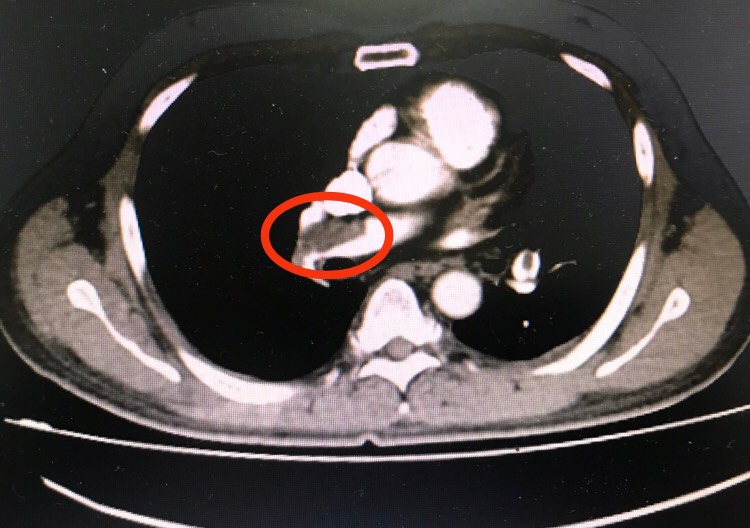

Hình ảnh cục máu đông của bệnh nhân Lê Văn H.trên phim chụp cắt lớp vi tính

Sau thăm khám và làm các xét nghiệm cận lâm sàng, bệnh nhân được chẩn đoán: Huyết khối động mạch phổi, có huyết khối trong nhĩ phải. Tình trạng bệnh nhân rất nguy kịch do khối lượng huyết khối nhiều.